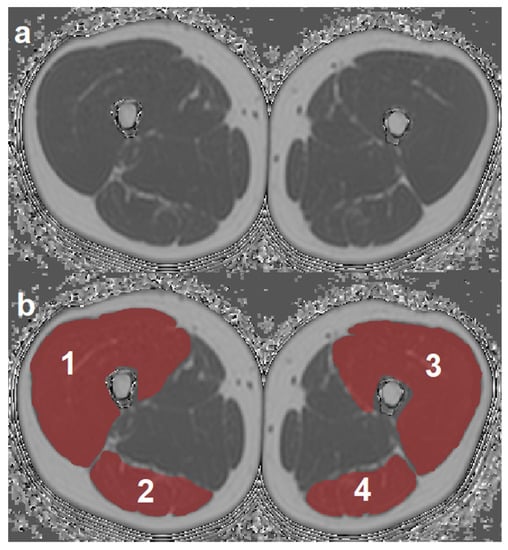

ROIs were placed at the muscle contour to minimize the inclusion of subcutaneous fat or the muscle–fat interface. A representative PDFF map with corresponding segmentation masks of EXT and FLEX muscles is shown in Figure 1. Mean PDFF of each of the four muscles was extracted. Mean PDFF values were calculated of EXT and FLEX for the left and right side, respectively, to obtain values for both muscle groups on both sides (PDFFEXT,left, PDFFEXT,right, PDFFFLEX,left, and PDFFFLEX,right). Sample color-coded PDFF maps of two subjects, one with high strength and low mean PDFF, and one with low-strength and high-mean PDFF are shown in Figure 2.

Figure 1.

Representative axial PDFF map (a) with overlays of the four segmented muscle ROIs (b). 1: right quadriceps muscle, 2: right ischiocrural muscles, 3: left quadriceps muscle, 4: left ischiocrural muscles. (PDFF, proton density fat fraction; ROI, region of interest).

In the last years, the application of texture features for advanced quantitative analysis of medical imaging has been growing, with an emphasis on oncology [45,46,47]. In a study with 41 female subjects, Burian et al. demonstrated that PDFF-based TA of vertebral bone marrow is feasible and can differentiate pre- and postmenopausal women [30]. To the best of our knowledge, CSE-MRI-based TA of thigh muscles has not been performed previously. Yet, the relationship between MRI-based measurements of muscle composition and isokinetic strength measurements has been investigated before. For thigh muscles, previous work shows that mean PDFF inversely correlates with isokinetic strength and improves the prediction of isokinetic strength beyond CSA [16,18]. This improved predictive power of mean PDFF was also demonstrated in paraspinal muscles [19]. The mentioned studies inspire the hypothesis that muscle composition is at least as important as pure muscle volume as a determinator of muscle function, and the two parameters CSA and mean PDFF may complement each other with respect to the prediction of muscle strength. Furthermore, in patients with neuromuscular disorders, an inverse relationship of thigh muscle PDFF and strength was shown [11,48]. The multivariate linear regression analyses performed in the present study revealed different results for the two analyzed thigh muscle groups. Sex and Variance(global)EXT, but not PDFF, were identified as significant predictors of extension strength, while sex, BMI, and PDFFFLEX, but none of the analyzed texture features, were identified as significant predictors of flexion strength. Hence, texture features improve the prediction of muscle strength beyond mean PDFF in the extensor compartment of the thigh. Based on the hypothesis that TA of muscle tissue derived from PDFF maps can quantify the distribution of muscle fat, this may be explained by a different pattern of MFI of the two muscular compartments, de facto meaning that TA can potentially differentiate quadriceps muscles with the same mean fat fraction but different pattern of fat infiltration, i.e., homogeneous vs. heterogeneous (e.g., in the form of fat streaks). However, we could not find a significant improvement of muscle strength prediction for the flexor muscles, which could have various explanations. In this context, differences between the two compartments regarding anatomy, such as number of involved joints (quadriceps: one joint vs. ischiocrural muscles: two joints), muscle volume and concomitant partial volume effects (quadriceps: high vs. ischiocrural: low volume; Figure 1), as well as physiology, such as neuromuscular activation (quadriceps: one peripheral nerve (N. femoralis) vs. ischiocrural: two peripheral nerves (N. tibialis, N. fibularis communis)) should be considered. The relatively small sample size of the study, potentially resulting in insufficient statistical power to demonstrate a significant effect for the flexor muscles, has to be acknowledged as well.

There are limitations to the present study. First, the study cohort comprises only a rather small number of young and healthy subjects featuring a relatively low mean and narrow distribution of PDFF values. Regardless of the low variation in muscle fat content, we observed significant correlations of texture features and strength measurements in both thigh muscle compartments. This leaves room for the interpretation that even small changes in muscle composition are reflected by structural changes, which exert a relevant effect on the biomechanical function of the muscle. As a next step, future studies covering a broader age spectrum and relevant patient cohorts (e.g., neuromuscular, musculoskeletal, or metabolic disorders) are needed to (i) confirm our initial results, and (ii) further investigate the potential of CSE-MRI-based muscle TA in disease, thus deepening the knowledge of thigh muscle quality and (dys-)function. This could translate into improved detection of pathologic muscle alterations and MFI at an early stage of disease. Second, TA performed in the present study included only a limited number of texture features. Extending the TA through the inclusion of additional texture operators, such as rotationally invariant local binary patterns, could reveal even more information on muscle structure [49]. Third, the muscle ROIs were segmented as a whole, which means that both intra- and intermuscular adipose tissue (intraMAT, interMAT) contribute to the PDFF distribution and could consequentially affect the TA results. However, given the resolution and image quality of the acquired images (Figure 1), an accurate segmentation of the single components of the quadriceps and ischiocrural muscles and subsequent exclusion of intraMAT was not practical. As far as feasible with regard to signal-to-noise ratio and acquisition time, adjusting the MRI sequence parameters should be considered in future studies, to enable more detailed muscle segmentation excluding interMAT.